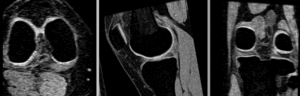

BSpline registration of full volumes. 9 x 9 x 5 gridBSpline registration of full volumes. 9 x 9 x 5 grid

• Phase 4: BSpline alignment

4. Registration Parameters: set "Number of Samples" to 300,000 at least

5. Number of Grid Subdivisions: 7,7,5

6. Maximum B-Spline Displacement: set to 5 [mm]